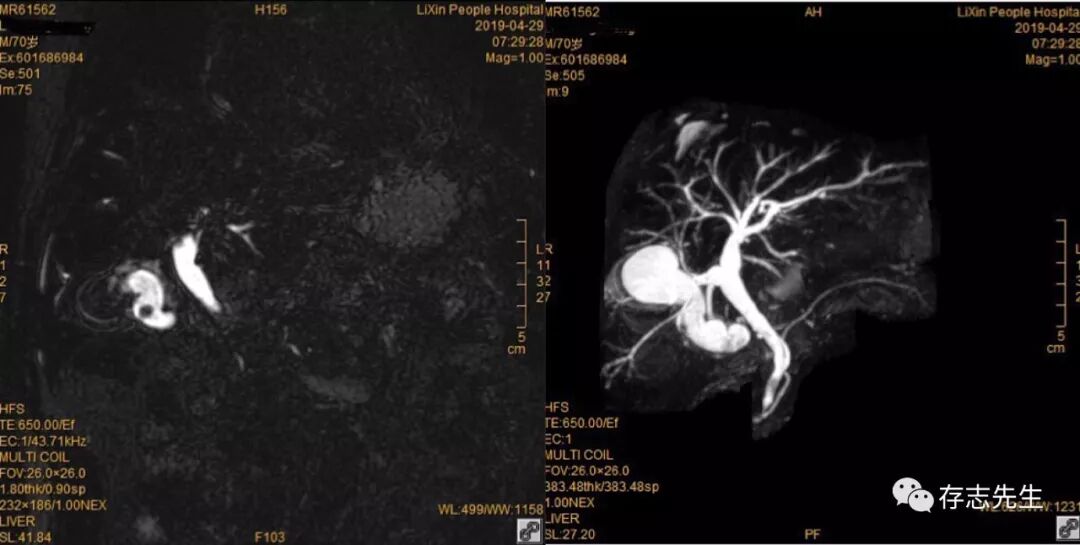

腹水

根据我的个人经验来说体型过胖和体型太瘦的患者,行MRCP检查的效果都不理想,体型过胖的患者脂肪厚的原因导致图像信号衰弱。体型过瘦的患者易产生较多的呼吸运动伪影。